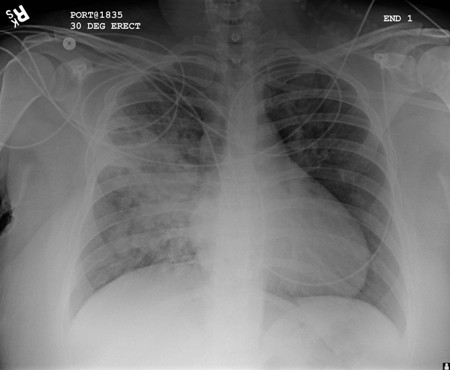

Chest x-ray

A chest x-ray should be obtained early in the evaluation of chronic cough.[38] Although it is not diagnostic of the most common causes, findings may quickly divert the evaluation to causes of greater gravity, such as structural lung diseases. These include lung cancer, pulmonary fibrosis, tuberculosis, bronchiectasis, pneumonia, aspiration, and sarcoidosis.[Figure caption and citation for the preceding image starts]: Chest x-ray showing hyperinflation in a patient with COPD. The hyperinflation is caused by the emphysema component of COPD, rather than the chronic bronchitis that underlies symptoms of coughFrom the personal collection of Dr M. A. Sharifabadand, SUNY at Stony Brook School of Medicine, Department of Pulmonary and Critical Care Medicine, Mineola, New York and Dr J. P. Parsons, The Ohio State University Medical Center, Columbus; used with permission [Citation ends].com.bmj.content.model.assessment.Caption@65a65855[Figure caption and citation for the preceding image starts]: Chest x-ray showing multiple miliary lung metastases (arrows). The primary tumour was a thyroid carcinomaE. Dick, Student BMJ. 2001;9:10-12 [Citation ends].com.bmj.content.model.assessment.Caption@25657fee[Figure caption and citation for the preceding image starts]: Chest x-ray showing left hilar carcinoma (arrow)From: E. Dick, Student BMJ. 2000;8:358-360 [Citation ends].com.bmj.content.model.assessment.Caption@567b9fef[Figure caption and citation for the preceding image starts]: Chest x-ray showing a cavitating right hilar carcinoma (arrow)E. Dick, Student BMJ. 2001;9:10-12 [Citation ends].com.bmj.content.model.assessment.Caption@3d6fa55[Figure caption and citation for the preceding image starts]: Chest x-ray in a patient with bronchogenic carcinoma showing a left-sided pleural effusionFrom: R. Thakkar, Student BMJ. 2001;9:458 [Citation ends].com.bmj.content.model.assessment.Caption@5b46acec[Figure caption and citation for the preceding image starts]: Chest x-ray showing interstitial fibrosis in a patient with amiodarone pulmonary toxicityFrom the personal collection of Dr A. Pataka and Professor P. Argyropoulou, Aristotle University, Thessaloniki, Greece; used with permission [Citation ends].com.bmj.content.model.assessment.Caption@2c3c94b0[Figure caption and citation for the preceding image starts]: Chest x-ray showing pulmonary tuberculosis with cavitationFrom the personal collection of Dr M. Narita, Department of Pulmonary and Critical Care Medicine, University of Washington [Citation ends].com.bmj.content.model.assessment.Caption@3dd7f84b[Figure caption and citation for the preceding image starts]: Chest x-ray showing multiple discrete nodules throughout both lungs (one of which is circled) in a patient with miliary tuberculosisE. Dick, Student BMJ. 2001;9:10-12 [Citation ends].com.bmj.content.model.assessment.Caption@23fa6365[Figure caption and citation for the preceding image starts]: Chest x-ray with lack of normal tapering producing a tram line in a patient with bronchiectasisFrom the personal collection of Dr S.M. Bhorade, University of Chicago Medical Center; used with permission [Citation ends].com.bmj.content.model.assessment.Caption@36b415f2[Figure caption and citation for the preceding image starts]: Chest x-ray with dilated and thickened airways in a patient with bronchiectasisFrom the personal collection of Dr S.M. Bhorade, University of Chicago Medical Center; used with permission [Citation ends].com.bmj.content.model.assessment.Caption@78e208fa[Figure caption and citation for the preceding image starts]: Chest x-ray showing increased opacification of the right perihilar region and superior segment of the right lower and upper lobes consistent with worsening aspiration pneumoniaFrom the personal collection of Dr R. Kanner, University of Utah School of Medicine [Citation ends].com.bmj.content.model.assessment.Caption@71be2c1f[Figure caption and citation for the preceding image starts]: Portable chest x-ray with bibasilar opacities, worse on the right than the left, in a patient with hospital-acquired pneumoniaFrom the personal collection of Dr F. W. Arnold, Division of Infectious Diseases, Department of Medicine, University of Louisville School of Medicine [Citation ends].com.bmj.content.model.assessment.Caption@2c704497[Figure caption and citation for the preceding image starts]: Chest x-ray showing early ill-defined opacities of the right upper lobe above the minor fissure consistent with early changes of aspiration pneumoniaFrom the personal collection of Dr R. Kanner, University of Utah School of Medicine [Citation ends].com.bmj.content.model.assessment.Caption@23fa54d0[Figure caption and citation for the preceding image starts]: A. Portable upright chest x-ray before aspiration; B. Chest x-ray 1 hour after aspiration, showing bilateral diffuse alveolar infiltrates, worse at the bases on the right sideFrom the personal collection of Dr S. Murgu and Dr H. Colt, University of California at Irvine Medical Center [Citation ends].com.bmj.content.model.assessment.Caption@7860be3a[Figure caption and citation for the preceding image starts]: Chest x-ray showing bilateral hilar adenopathy in a patient with sarcoidosisFrom the personal collection of Dr M.P. Muthiah, Division of Pulmonary and Critical Care and Sleep Medicine, University of Tennessee [Citation ends].com.bmj.content.model.assessment.Caption@31e94b4e